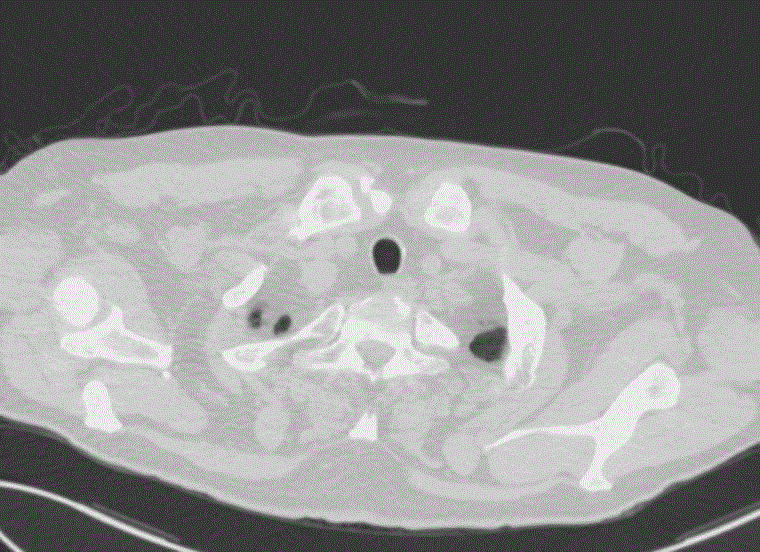

一、肺癌

在中国,肺癌的发病率和死亡率均高居恶性肿瘤榜首。早期发现最有效的手段,就是筛查。通常建议至少50岁要开始筛查,可根据个体意愿可恰当提前至45岁或40岁开始筛查。

1.重点筛查项目:胸部低剂量螺旋CT扫描

胸部CT

对于高风险人群,建议每年一次胸部低剂量螺旋CT,选择薄层胸部CT平扫也可以,不推荐拍胸片。胸片很难发现早期小结节,容易漏诊。